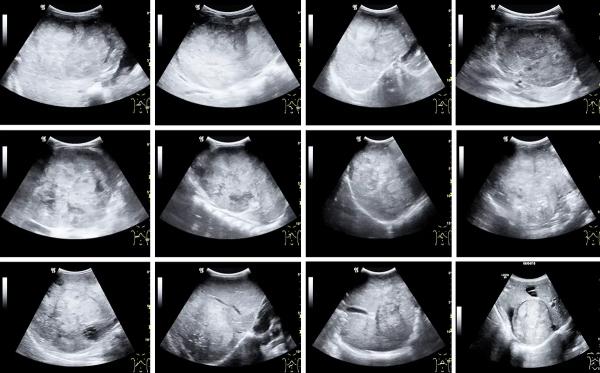

После установления диагноза нефробластомы УЗИ используется для мониторинга эффективности лечения и оценки изменений в размере и структуре опухоли после химиотерапии. Сонографические варианты впервые выявленной нефробластомы представлены на рисунке 2.

Рисунок 2. Сонографические варианты первично диагностируемой нефробластомы. Это преимущественно солидные опухоли почек больших размеров. Билатеральный вариант поражения — снимок во втором ряду крайний справа, кистозный вариант — в третьем ряду крайний справа, с субкапсульной гематомой почки — второй снимок во втором ряду.